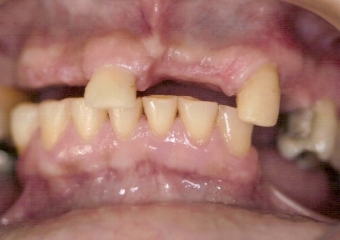

Sorriso Inicial